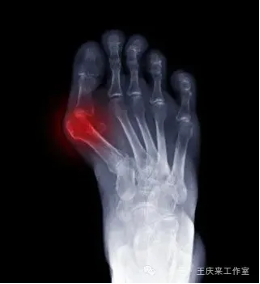

拇外翻,又称“大脚骨”,是指大脚趾向外倾斜超过了正常生理范围,通常伴有第一跖骨头内侧的骨赘形成。它的成因多种多样,遗传、穿着不合适的鞋子(尤其是高跟鞋)、足部韧带松弛、长期站立或行走等都是诱发因素。初期可能仅表现为外观异常,随着病情发展,可能会伴随疼痛、红肿、走路困难等症状。

手术治疗:对于中重度拇外翻或保守治疗无效者,可能需要通过手术纠正拇趾位置。手术方式有许多种,主要目的是切除增生的骨赘,重建相关韧带结构,以恢复正常步态和缓解疼痛。